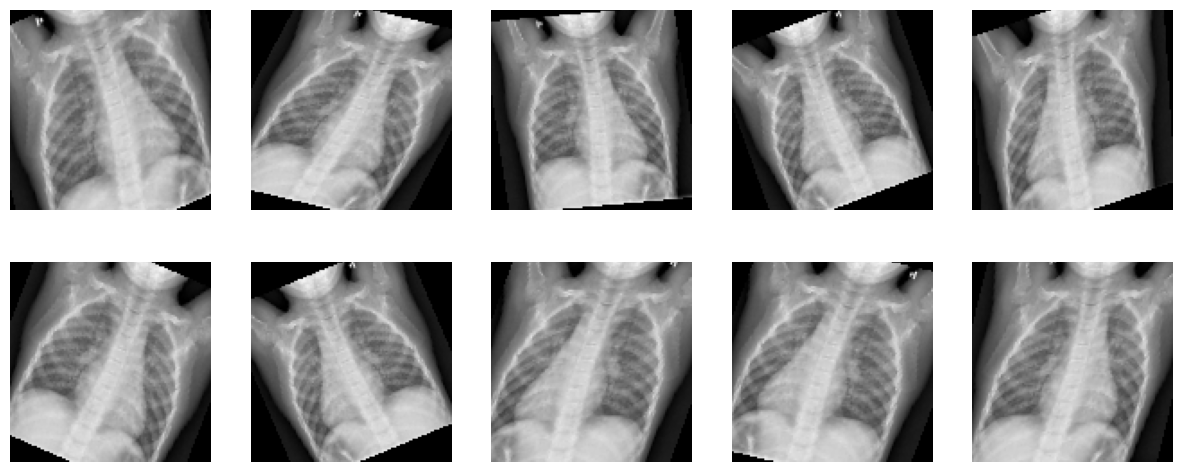

Apply transformation to one image and see the result of ten calls to the transform function we described.

plt.figure(figsize=(15,6))

for i in range(10):

image = transform(nimage)

plt.subplot(2,5,i+1)

img = image.cpu().detach().numpy().transpose((1, 2, 0))

plt.axis('off')

plt.imshow(img)

../_images/9821ef29307c204b7b4151a8fd9369c181ff32a63ba19958daed027377c9d16e.png